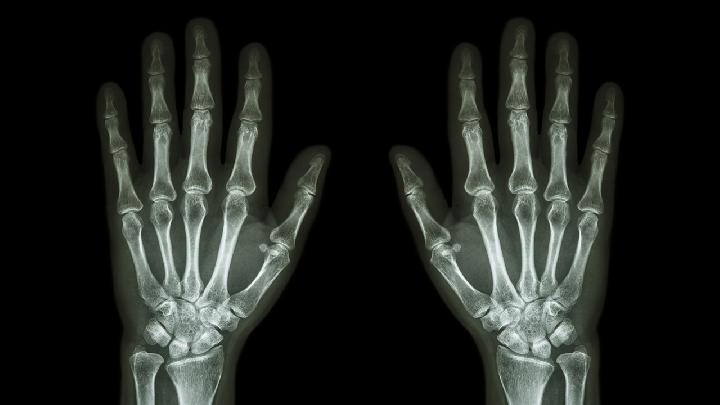

蹲下去膝盖会痛很有可能是患上了膝关节髌骨关节炎。膝关节的髌骨和股骨之间如果存在着慢性炎症,那么就容易造成软骨损伤,这样一来,在下蹲的时候就会感觉膝关节疼痛。建议尽早做膝关节X线片检查,有必要的话也可以做核磁共振检查来进行诊断。

膝关节炎是一种非常严重的疾病,中老年人是膝关节炎的高发人群,为此在生活当中大家不仅要做好膝关节炎的预防工作,同时还要多了解一些有关膝关节炎的检查方法,对早期确诊断膝关节炎会有一定的帮助,那么,检查膝关节炎项目有哪些?我们一起来看看吧。